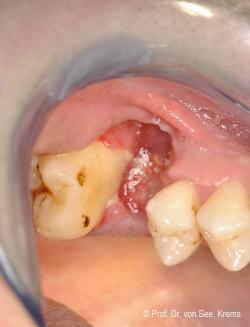

Wirken diese Kräfte in direkter Nachbarschaft zu einem dentalen Implantat ein, stellt sich die Frage, was mit dem Knochen am Implantat passiert. Dieser ist nicht mittels eines Faserapparates an das Implantat angebunden, sondern steht in direktem Kontakt zu diesem. Wenn jetzt Zugkräfte auf den Knochen einwirken, so folgt dieser der Zahnbewegung. Durch orthodontische Zahnbewegung in direkter Nachbarschaft zu einem Implantat kann ein Knochenabbau induziert werden, der eine umfangreiche weitere Behandlung erfordert und in aufwendigen Maßnahmen zur prothetischen Rehabilitation enden kann.

Der in diesem Beitrag vorgestellte Fall macht dieses deutlich.